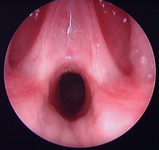

Laryngeal appearance after supraglottoplasty using cold steel

From the personal teaching collection of Simone J. Boardman, MBBS, FRACS (OHNS) and C. Martin Bailey, BSc, FRCS, FRCSEd

See this image in context in the following section/s: